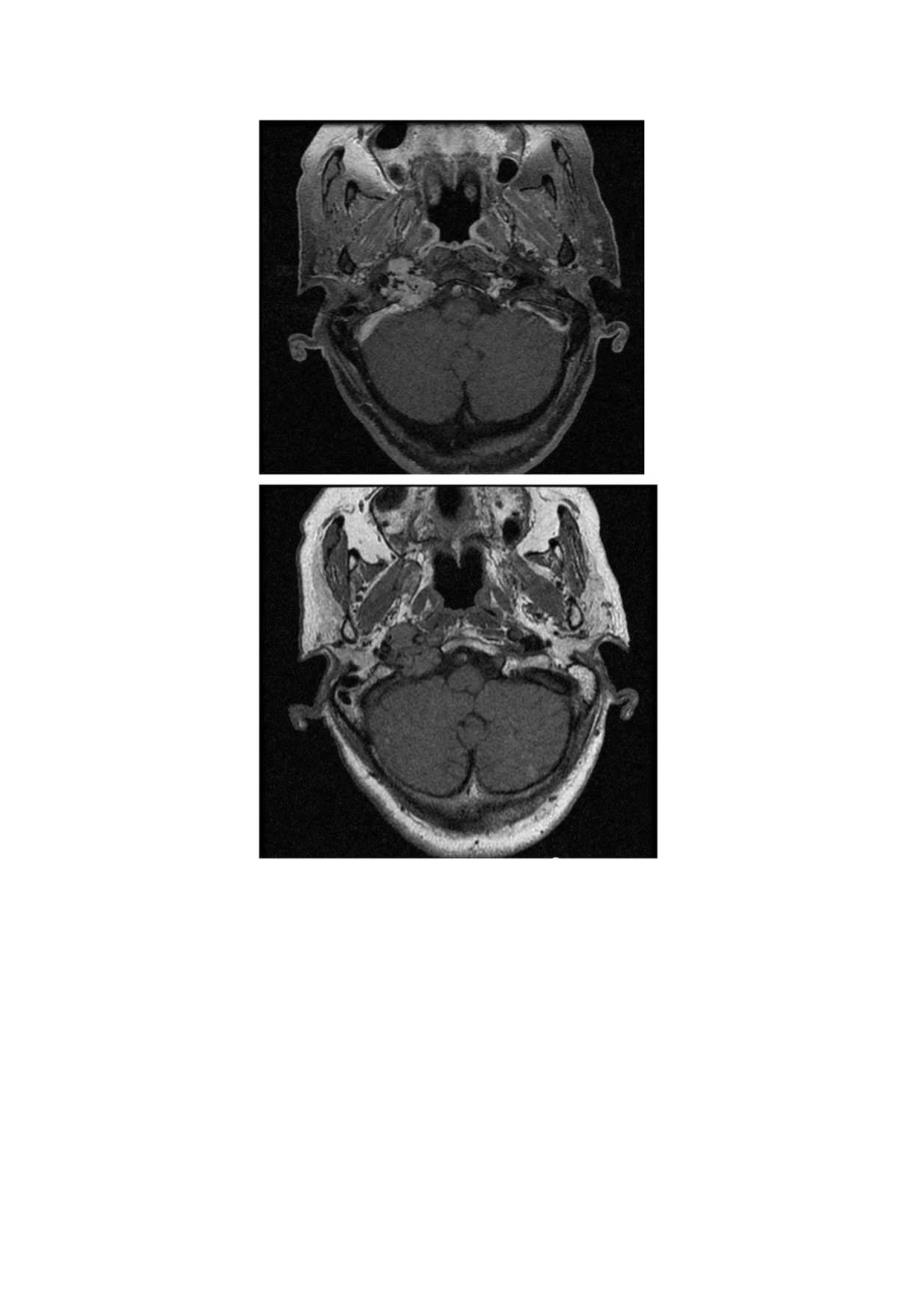

1、胡椒盐征影像表现、临床病理及鉴别诊断胡椒盐征:血管球瘤中有多数迂曲条状及点状血管流空影,MRI增强扫描不强化,肿瘤实质明显强化,称为“椒盐”征。“椒”是低信号血管流空影;“盐”是指高信号的点状出血。横断位所见患者女性,72岁,反复头痛、耳鸣1年余,加重1周。更为形象的TOF-MRAP同一患者CT分析与讨论颈静脉球瘤,起源于颈静脉球壁的化学感受器,属副神经节细胞来源的一类非嗜倍性副神经节瘤(化学感受器瘤),为良性血管性肿瘤,但其生长方式呈恶性。多为无功能性肿瘤,功能性颈静脉球瘤少见。嗜倍性副神经节瘤好发于肾上腺,也叫嗜倍细胞瘤。非嗜倍性副神经节瘤(化学感受器瘤),好发于头颈部,如颈动脉分叉(即颈

2、动脉体瘤)、颈部迷走神经、颈静脉球(即颈静脉球瘤)和中耳鼓室(鼓室球瘤),少数来自鼻咽、喉腔、翼腭窝等。在MRl检查中,颈静脉球瘤除发生部位较特殊外,信号变化,内部血管结构和增强强化形式等有助于该病的诊断。肿瘤实质在T2WI则多数呈明显高信号,TlWI多呈中等或偏低信号,TIWl增强扫描呈明显均匀强化,在多个序列中可见椒盐征,即在肿瘤实质中可见点,条状的无信号流空血管影。肿瘤直径较大时出现此征象的几率高,MRA可发现瘤区有异常血管。在病理组织学上,肿瘤由I型的主细胞和Il型支持细胞构成,主细胞簇由富含大量血管腔的纤维基质分隔,这些血管形成很多毛细血管前动、静脉瘦,这些组织、病理学特点是该类肿瘤MR信号变化及椒盐征的基础。鉴别诊断:1、脑膜瘤:发生颈静脉孔区的脑膜瘤需同颈静脉球瘤鉴别。脑膜瘤多数信号常较均匀,在T2WI上信号多为等或稍高信号,TlWI上多为等或稍低信号,增强扫描常明显均匀强化,有时可见钙化、脑膜尾征等,囊变少见。2、2、IXXl对颅神经起源的肿瘤神经瘤:二者鉴别较困难,较大的神经鞘瘤坏死、囊变常见,而颈静脉球瘤坏死囊变较少,常见椒盐征。